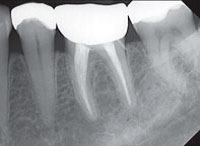

Цифровая  компьютерная   диагностика.

В нашей работе мы используем радиовизиограф HELIODENTPLUS – это интраоральная рентгенографическая система новейшего поколения немецкой фирмы «Sirona» дающая  высокое качество изображения при минимальной дозе облучения, что позволяет нам проконтролировать качество проведенного лечения.

Рентгеновские изображения, полученные на HELIODENT

PLUS, характеризуются высокой детализацией и контрастностью, что позволяет использовать их по широкому ряду показаний.

Рентгенологические методы исследования являются незаменимыми в качестве диагностического инструмента. На сегодняшний день многие врачи используют далеко не все возможности рентгеновского исследования. А между тем это позволяет не только верно планировать лечение, но и достичь стабильных функциональных и эстетических результатов.